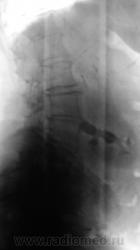

Пациентка была направлена неврологом на рентгенографию поясничного отдела позвоночника по поводу болей в "пояснице".

Произведена стандартная рентгенография.

S-образный сколиоз II ст. Остеохондроз III ст, спондилоартроз. Коралловидный камень правой почки.

А, ведь долгое время, эту пожтлую даму, пользовали по поводу вертебральной патологии.